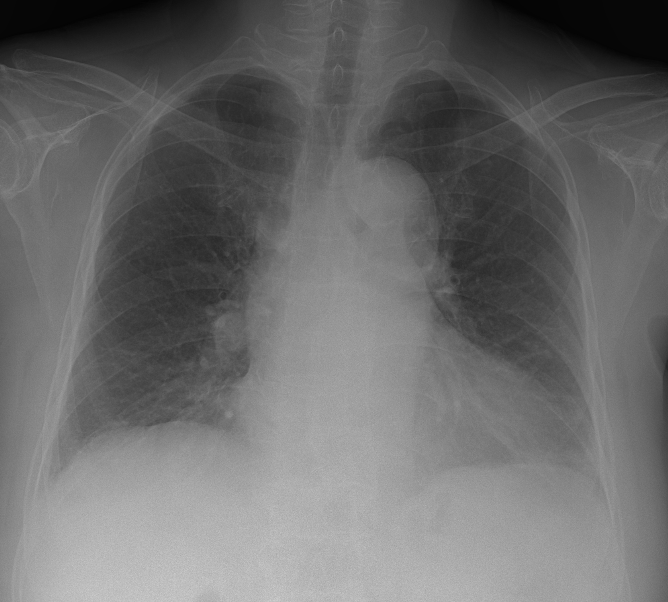

<³»¿ø½Ã CXR>

<3³âÀü CXR>